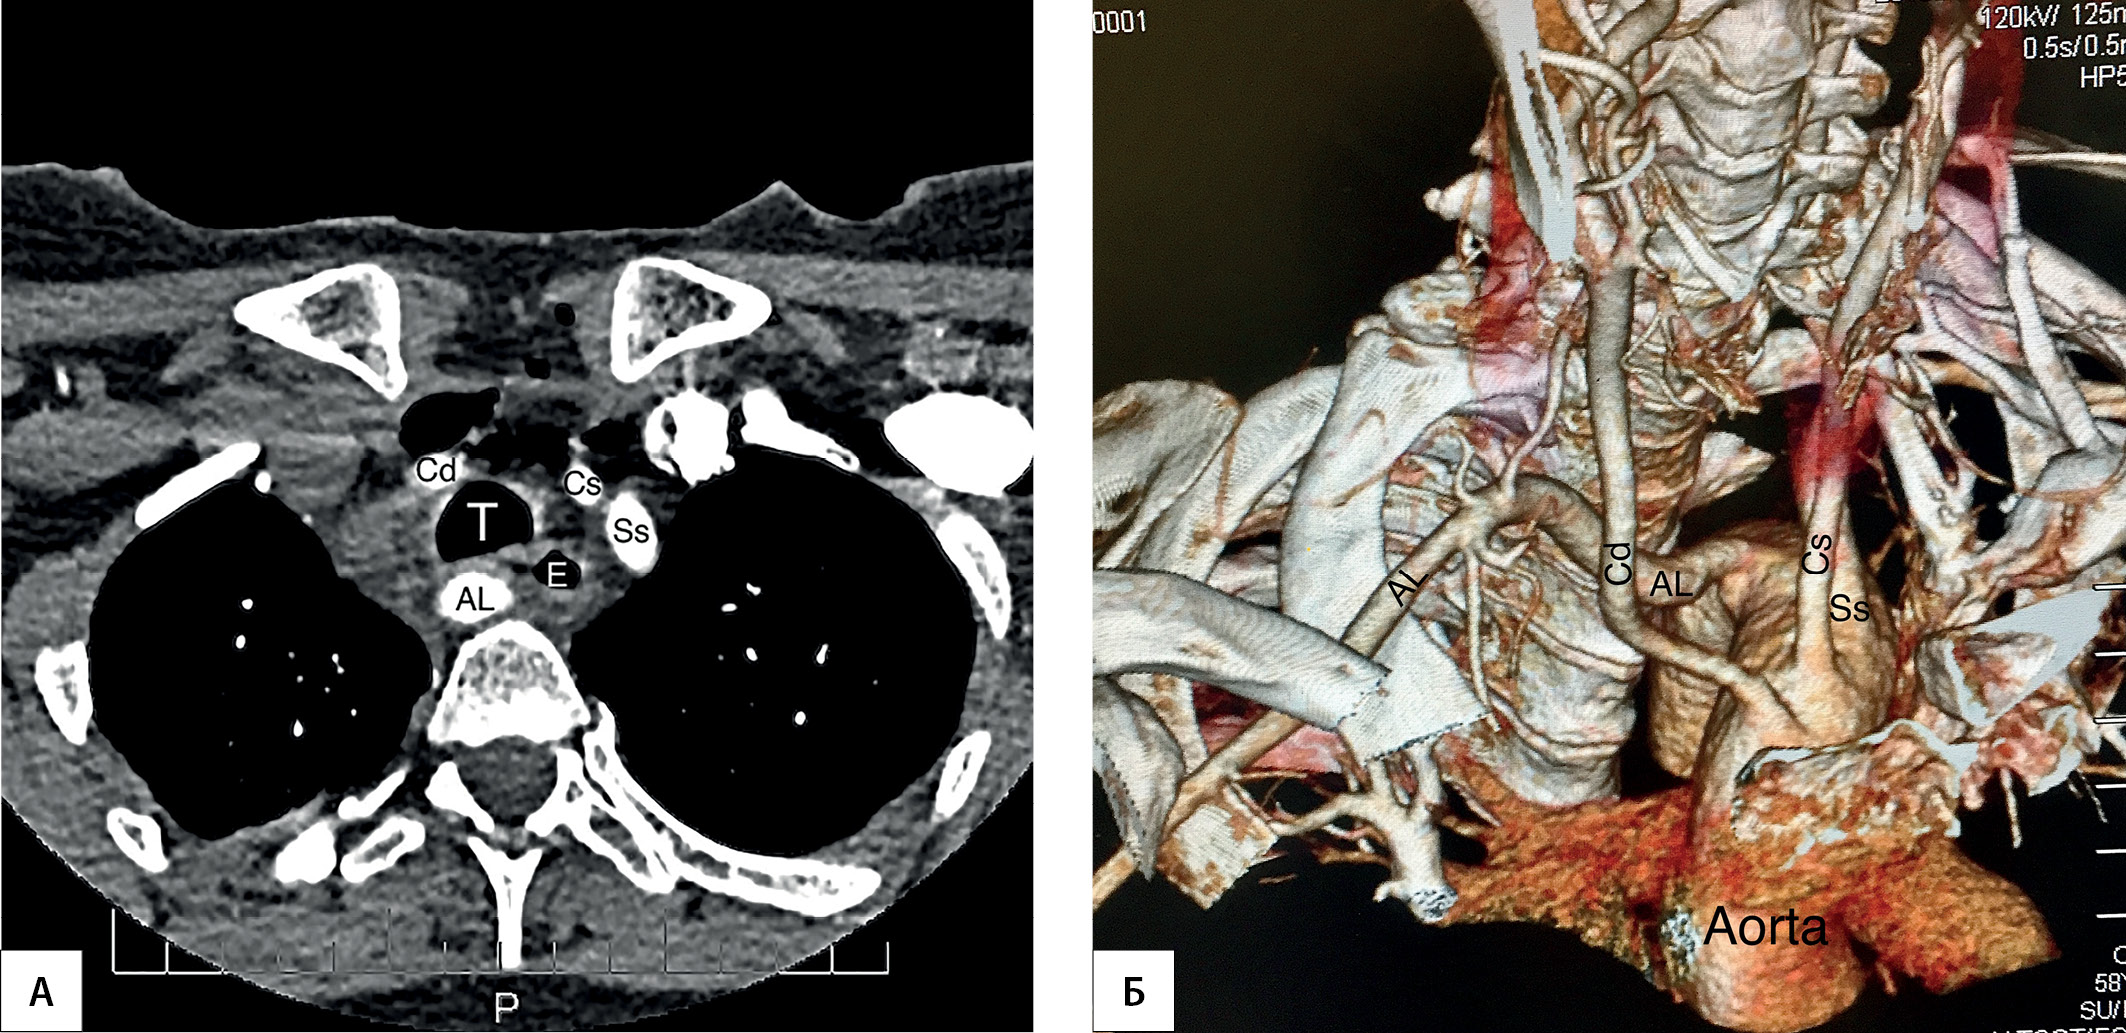

ОБОСНОВАНИЕ. Основной причиной послеоперационных парезов и параличей гортани является вариационная анатомия возвратного гортанного нерва. Примером такой «крайней формы индивидуальной изменчивости» является невозвратный гортанный нерв. Однако данная структура считается редкой аномалией с частотой встречаемости в популяции менее 0,5%. Именно с этим ошибочным убеждением связывают 6–7-кратное увеличение числа парезов гортани при встрече хирурга с невозвратным гортанным нервом. Между тем в исследованиях на трупном материале продемонстрирована значительно более высокая распространенность невозвратного гортанного нерва — 2,2%. При компьютерной томографии брахиоцефальных сосудов правая аберрантная подключичная артерия диагностирована у 3,1% пациентов.

МАТЕРИАЛЫ И МЕТОДЫ. В исследование включены пациенты, которым выполнялись операции на щитовидной или околощитовидных железах с выделением правого нижнего гортанного нерва. В предоперационном периоде проводились УЗИ сосудов шеи с визуализацией брахиоцефального ствола (Y-признака) и правой аберрантной подключичной артерии (AL-признак). При интраоперационном выявлении невозвратного гортанного нерва в послеоперационном периоде проводилась компьютерная томография сосудов шеи.

РЕЗУЛЬТАТЫ. В исследование включены 1476 пациентов. Y-признак отмечен у 1338 (90,7%) пациентов. У данного контингента больных определялась типичная анатомия возвратного гортанного нерва. В 138 (9,3%) случаях Y-признак выявить не удалось. В этой подгруппе в 20 (1,4%) наблюдениях отмечены невозвратный гортанный нерв и правая аберрантная подключичная артерия. Таким образом, чувствительность Y-признака в диагностике нормальной анатомии возвратного гортанного нерва составила 100%, специфичность — 91,9%, положительная прогностическая ценность — 14,5%, отрицательная прогностическая ценность — 100%. Напротив, AL-признак отмечен у всех пациентов с невозвратным гортанным нервом и правой аберрантной подключичной артерией. Ложноположительных и ложноотрицательных результатов не отмечено. На основе анализа интраоперационных картин выделено три варианта невозвратного гортанного нерва: I тип (верхний) — расположен позади верхней трети доли щитовидной железы, имеет прямое нисходящее направление и образует угол к гортани в 30–50°; III тип (нижний) — имеет прямое восходящее направление (имитирует ход возвратного гортанного нерва) и образует угол к трахее в 30–50°; II тип (средний) — все варианты невозвратного гортанного нерва, расположенного между I и III типами.

ЗАКЛЮЧЕНИЕ. Выявление брахиоцефального ствола (Y-признака) при УЗИ подтверждает наличие у пациента возвратного гортанного нерва (чувствительность 100%), а визуализация правой аберрантной подключичной артерии (AL-признака) определяет наличие невозвратного гортанного нерва (чувствительность и специфичность 100%).

3. Рисунок 3. КТ-признаки AL. | |